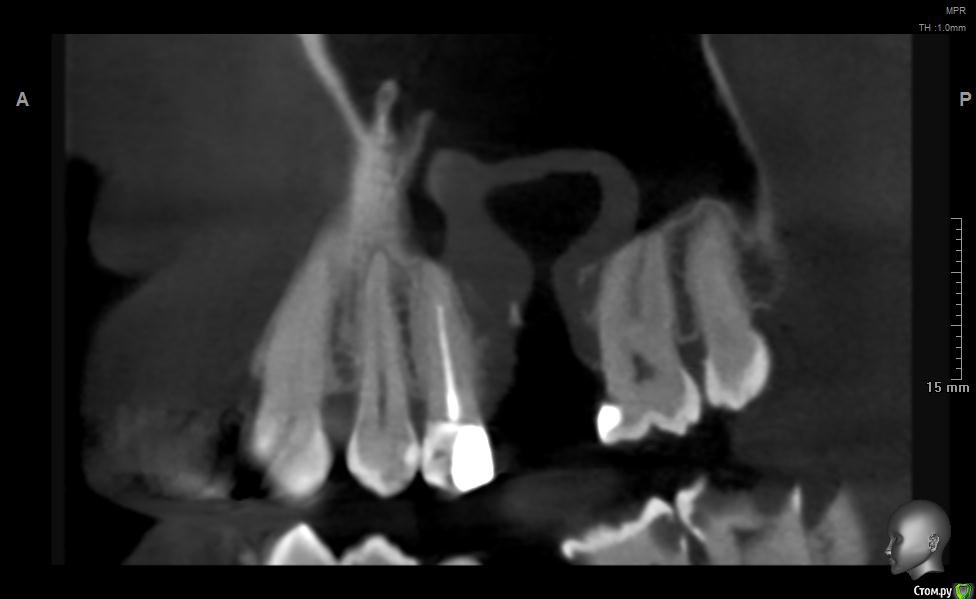

jm3300 Опубликовано 20 мая, 2019 Поделиться Опубликовано 20 мая, 2019 Добрый день. Пациент не мой, причины удаления, а так же о ходе удаления сказать ничего не могу. Известно лишь, что после удаления из лунки получили много зеленоватой жидкости. Удаляли с месяц назад. До сих пор имеется не сильно зияющая дырка. Нужно что то делать или просто ждать пока вторичным затянется. И если имплант планировать- ожидать ли там самостоятельного появления обьема кости? Ссылка на комментарий

L.E.S.I.K. Опубликовано 20 мая, 2019 Поделиться Опубликовано 20 мая, 2019 Я бы сделал ревизию через лунку, убрал оболочку кисты (похоже что она там осталась, или это эпителий врос - не важно) и провел бы закрытие небным лоскутом. При направлении в ЧЛХ есть вероятность, что наведут "разруху"(по Колддвел-Люк) и пациент получит проблему при дальнейшей реабилитации. З.Ы. На данных срезах не видно остиомеатальный комплекс- крайне желательно, чтобы он был не блокирован. 3 Ссылка на комментарий

Дмитрий М Опубликовано 21 мая, 2019 Поделиться Опубликовано 21 мая, 2019 месяц прошел, уже ничего не дождетесь, кость там не вырастет т.к. уже пошла эпителизация. так и останется не сильно зияющая дырка только вы видите клиническую картину, поэтому вам решать какой вариант лучше выбрать.в любом случае удалять кисту, оболочку, вероятно будет сообщение, которое необходимо закрывать и по ситуации готовиться к обоим вариантам по снимкам это скорее киста, (прослеживается кортикальная по контуру) 1 Ссылка на комментарий

Дмитрий Л. Опубликовано 21 мая, 2019 Поделиться Опубликовано 21 мая, 2019 Там уже есть сообщение с гайморовой. Возможно не функционирующее. Вяло текущий хронический воспалительный процесс. Ждать мало смысла. Если стремиться сделать всё как можно менее инвазивно, можно пойти по такому пути:1. Недельку попромывать соустье антисептиками. Воспаление стихнет. Десны добавится.2. Расскрыться. Аспирировать слизистую слюноотсосом. Кюретаж, всё через лунку. Если функционирующего соустья не было, оно появится.3. Небный лоскут, чтоб ушить соусье. Сосудосуживающие в нос, антибиотики. Ссылка на комментарий

jm3300 Опубликовано 21 мая, 2019 Автор Поделиться Опубликовано 21 мая, 2019 Ну по КТ и клинически сообщения с пазухой нет. Пациента,кроме наличия самой лунки, вообще ничего не беспокоит. Ссылка на комментарий